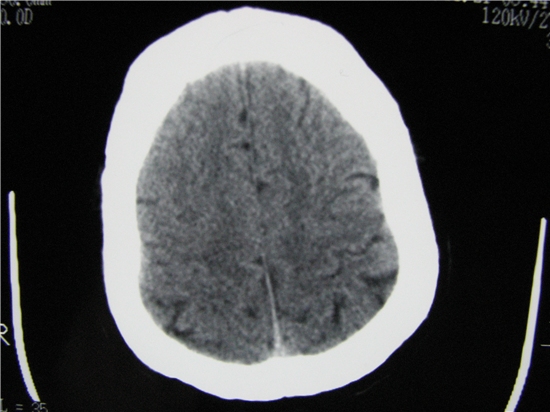

标题: CT23231:男 32岁 车祸伤,鼻腔内出血明显。 [打印本页]

标题: CT23231:男 32岁 车祸伤,鼻腔内出血明显。